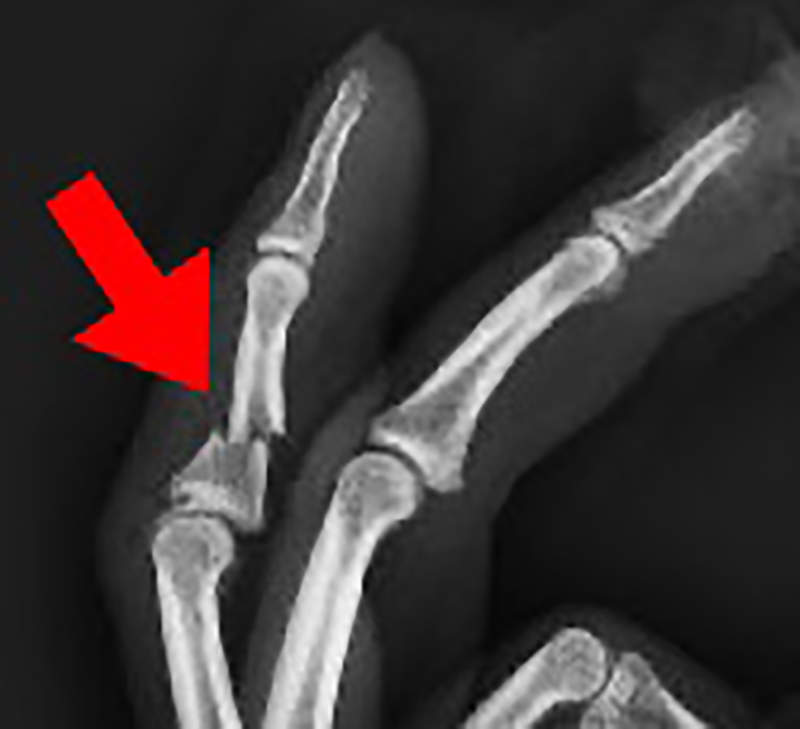

左手中指被咬到骨折

由於他的左手中指受傷最慘重,治療之後還是少了大約2公厘的長度……

被熊襲擊以後發生的事之4:左手中指短了一點